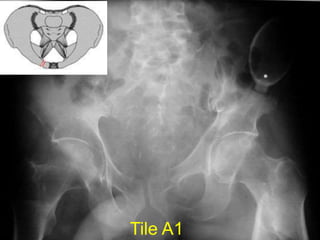

Tile A1

Type A1 avulsion